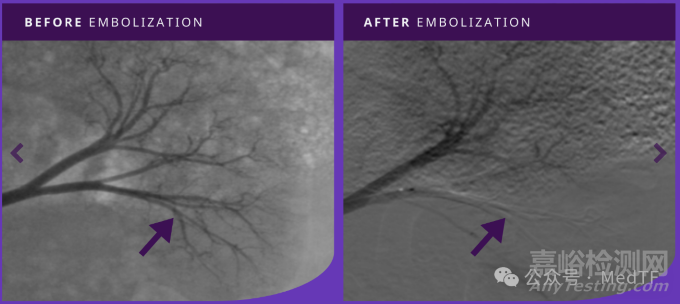

TEMBO栓塞左腎動(dòng)脈前后